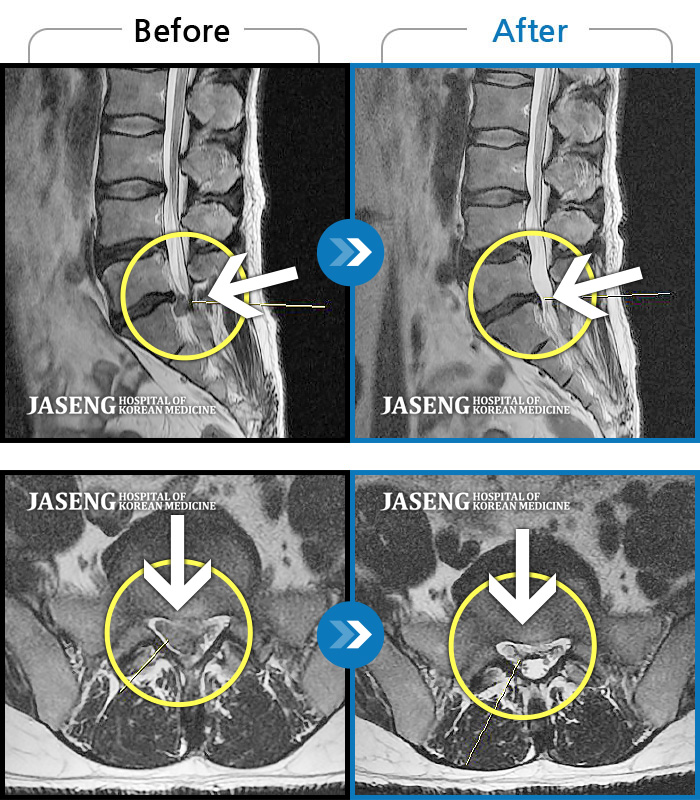

MRI ũ ʸ Ȯϼ.